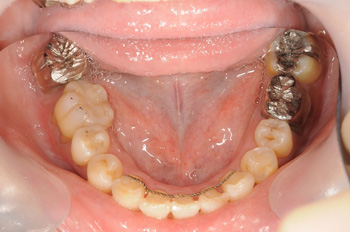

差し歯が外れて来院された患者様ですが、咬み合せが深く、しっかり咬めていなかったことから矯正治療できっちり治療する事にしました。

まずは歯列矯正にて歯並びを整えて、咬み合わせが整った上で補綴物をやり替える治療計画で進めていきました。

歯並びがしっかりと整いましたので不良補綴物のやり替えを行なっていきました。